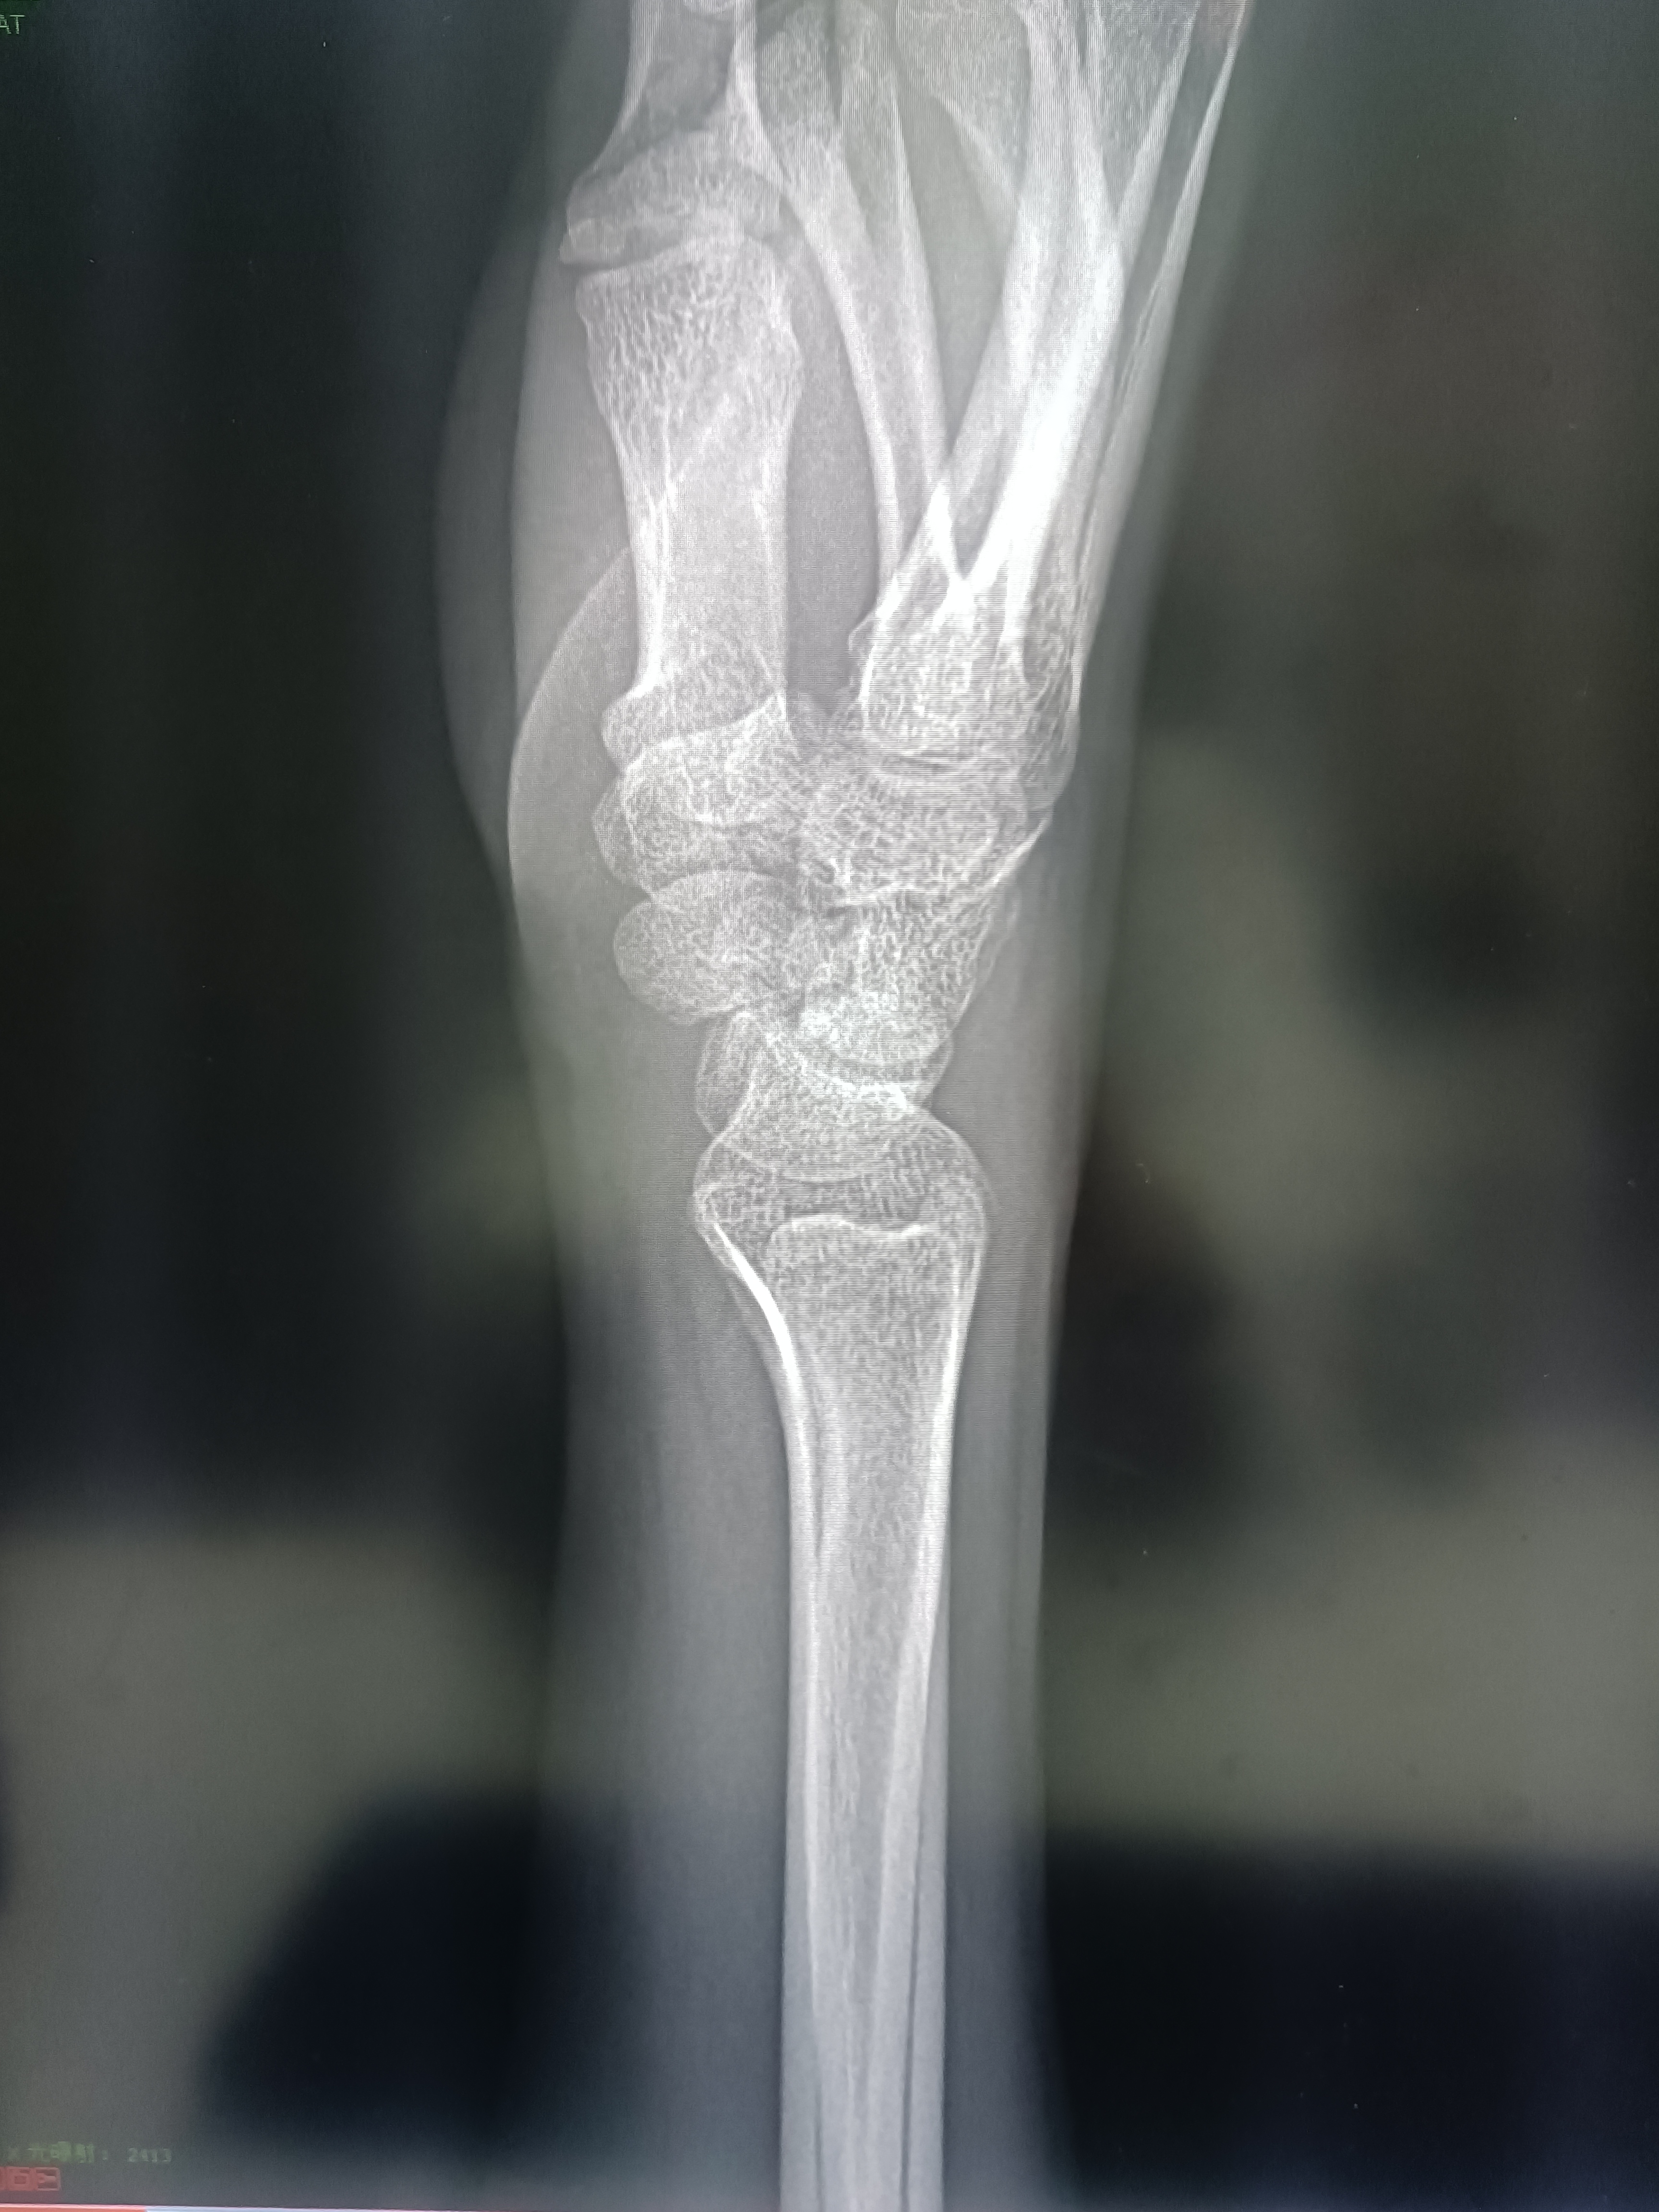

手腕部外伤,请观察一下有无骨折?

请观察手舟骨